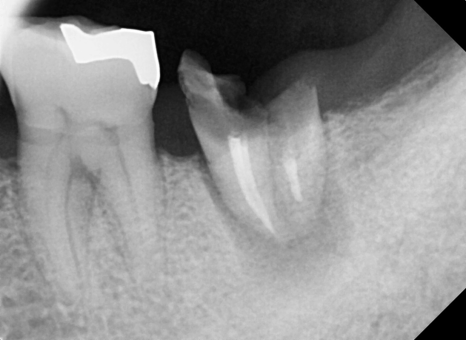

2달이 지났습니다. 임플란트가 잘 붙은것을 확인하고

임플란트 상부 보철물 제작을 진행합니다.

반대편에 고름주머니 잡힌 치아도 발치 즉시 식립으로 수술을 원하셔서

당일 수술 진행해 드렸습니다.

(이랫던 치아가... 30분이 지나면..)

요렇게 바뀝니다.

CT상으로 봐도 잘 들어갔군요.

주변부 뼈의 양도 골질도 매우 괜찮습니다.